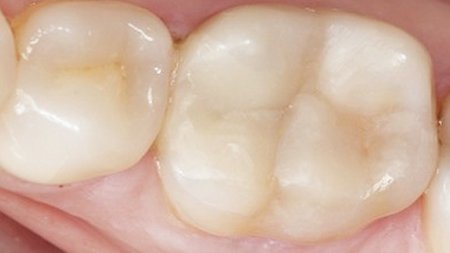

In 2010, an insufficient amalgam restoration in this first molar was replaced with condensable composite. Ten years later, it was again necessary to take action. Wear of the disto-occlusal surface resulted in dentin exposure in the composite restoration. The remaining enamel on the occlusal surface is visible. Due to sensitivity issues, the restoration was required. In addition, recurrent caries could be observed. Another contributing factor was the loss of occlusal contact caused by previous orthodontic treatment. The decision was made to reconstruct the tooth with a minimally invasive direct composite restoration.

Occlusal view of the initial situation on lower first molar.